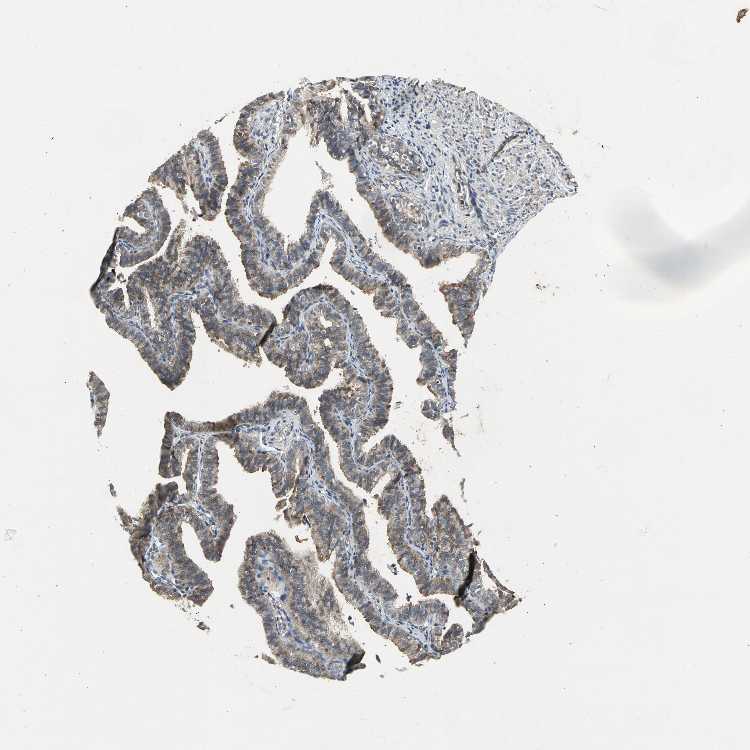

FALLOPIAN TUBE - Antibody stainingi

Antibody staining in the annotated cell types in the current human tissue is reported as not detected, low, medium, or high, based on conventional immunohistochemistry profiling in selected tissues. This score is based on the combination of the staining intensity and fraction of stained cells.

Each image is clickable and will lead to virtual microscopy that enables deeper exploration of all samples and also displays staining intensity scores, fraction scores and subcellular localization as well as patient and tissue information for each sample.

Antibody HPA029722Antibody HPA029723Antibody CAB005072

Ciliated cells (cell body) Not detected--

Ciliated cells (cilia axoneme) Not detected--

Ciliated cells (ciliary rootlets) Medium--

Ciliated cells (tip of cilia) Medium--

Glandular cells -LowMedium

Non-ciliated cells Medium--